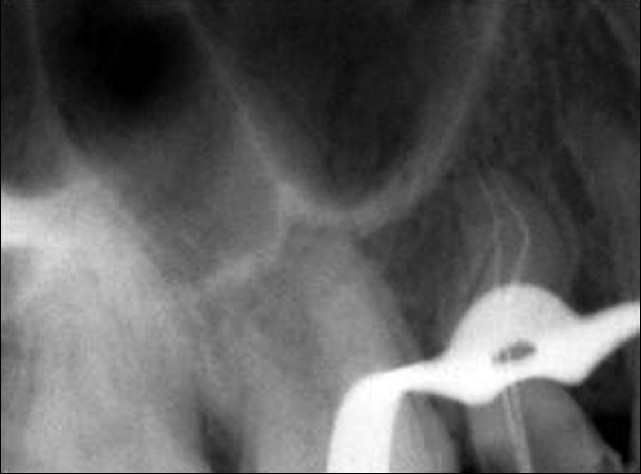

Unlike the buccal root, the palatal root was negotiable only up to the middle third of the root canal. There was resistance to the movement of the patency file. The palatal root canal was enlarged with protaper rotary instruments (Sx) in a crown down motion, right up to the straight portion of the canal. Once this was done, the patency file slid in easily, to the full length. The working length was established using an apex locator (Root ZX, J. Morita, Mfg. Corp, Japan) and confirmed using a radiograph [Figure 3]. The root canal was initially enlarged using NiTi hand files (MANI, Inc, Japan). Three percent NaOCl, EDTA and saline were used as irrigants. The apical portion of the palatal canal was prepared using short amplitude filing. The apical portion and the middle portion were merged using circumferential filing. Both the buccal and palatal canals were obturated using Guttapercha by cold lateral compaction technique [Figure 4].

Figure 3.

Working length radiograph